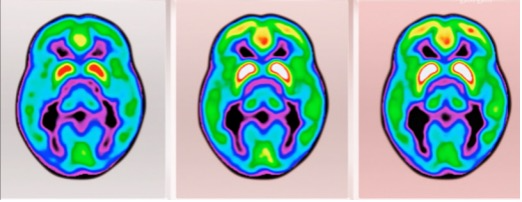

我们提到的第一个阶段,也即是Aβ的堆积,在40岁的时候就已经开始。这是一位遗传型病人从40到80岁的头部扫描,我们在40岁的扫描中已经能清楚地看到Aβ蛋白的堆积(蓝色区域),

而病人在70岁左右表现出症状时,Aβ的堆积几乎已经遍布全脑,在对记忆至关重要的海马体(hippocampus)附近更是已经非常集中,这基本上意味着在症状出现时,神经元早已经开始大面积地死亡。

此时的阿尔茨海默症,已经像泰坦尼克号船头前的冰山一样,完全没有避开的可能了。